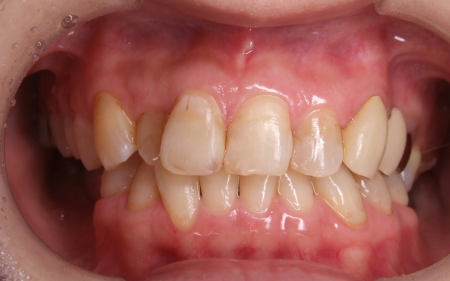

拝見したところ、歯と歯が並ぶ土台の骨「歯槽基底」の大きさの不調和により歯並びがガタガタになる「叢生(そうせい)」が全体的に生じており、また上下の前歯の重なりが深いため下の歯が見えない「過蓋咬合(かがいこうごう)」も認められました。

下の奥歯5本(右第2小臼歯/5番、左右第1大臼歯/6番、左右第2大臼歯/7番)が欠損したまま長く放置されていたことが原因で、噛み合う歯がなかった左上の奥歯(第1大臼歯)は本来の位置より下に伸びる「挺出(ていしゅつ)」が起き、左下の歯2本(第1小臼歯/4番、第2小臼歯)も内側に倒れたことで、下前歯の叢生が悪化したと考えられます。

さらに左上の歯(第1小臼歯)の欠損部位は両隣の歯2本(犬歯/3番、第2小臼歯)を土台に人工歯を橋渡しにする被せ物「ブリッジ」が装着されており、お口を開けたときに銀歯が目立つことに加えて、歯の色が全体的に黄ばんでいるため見た目が良くない状態でした。